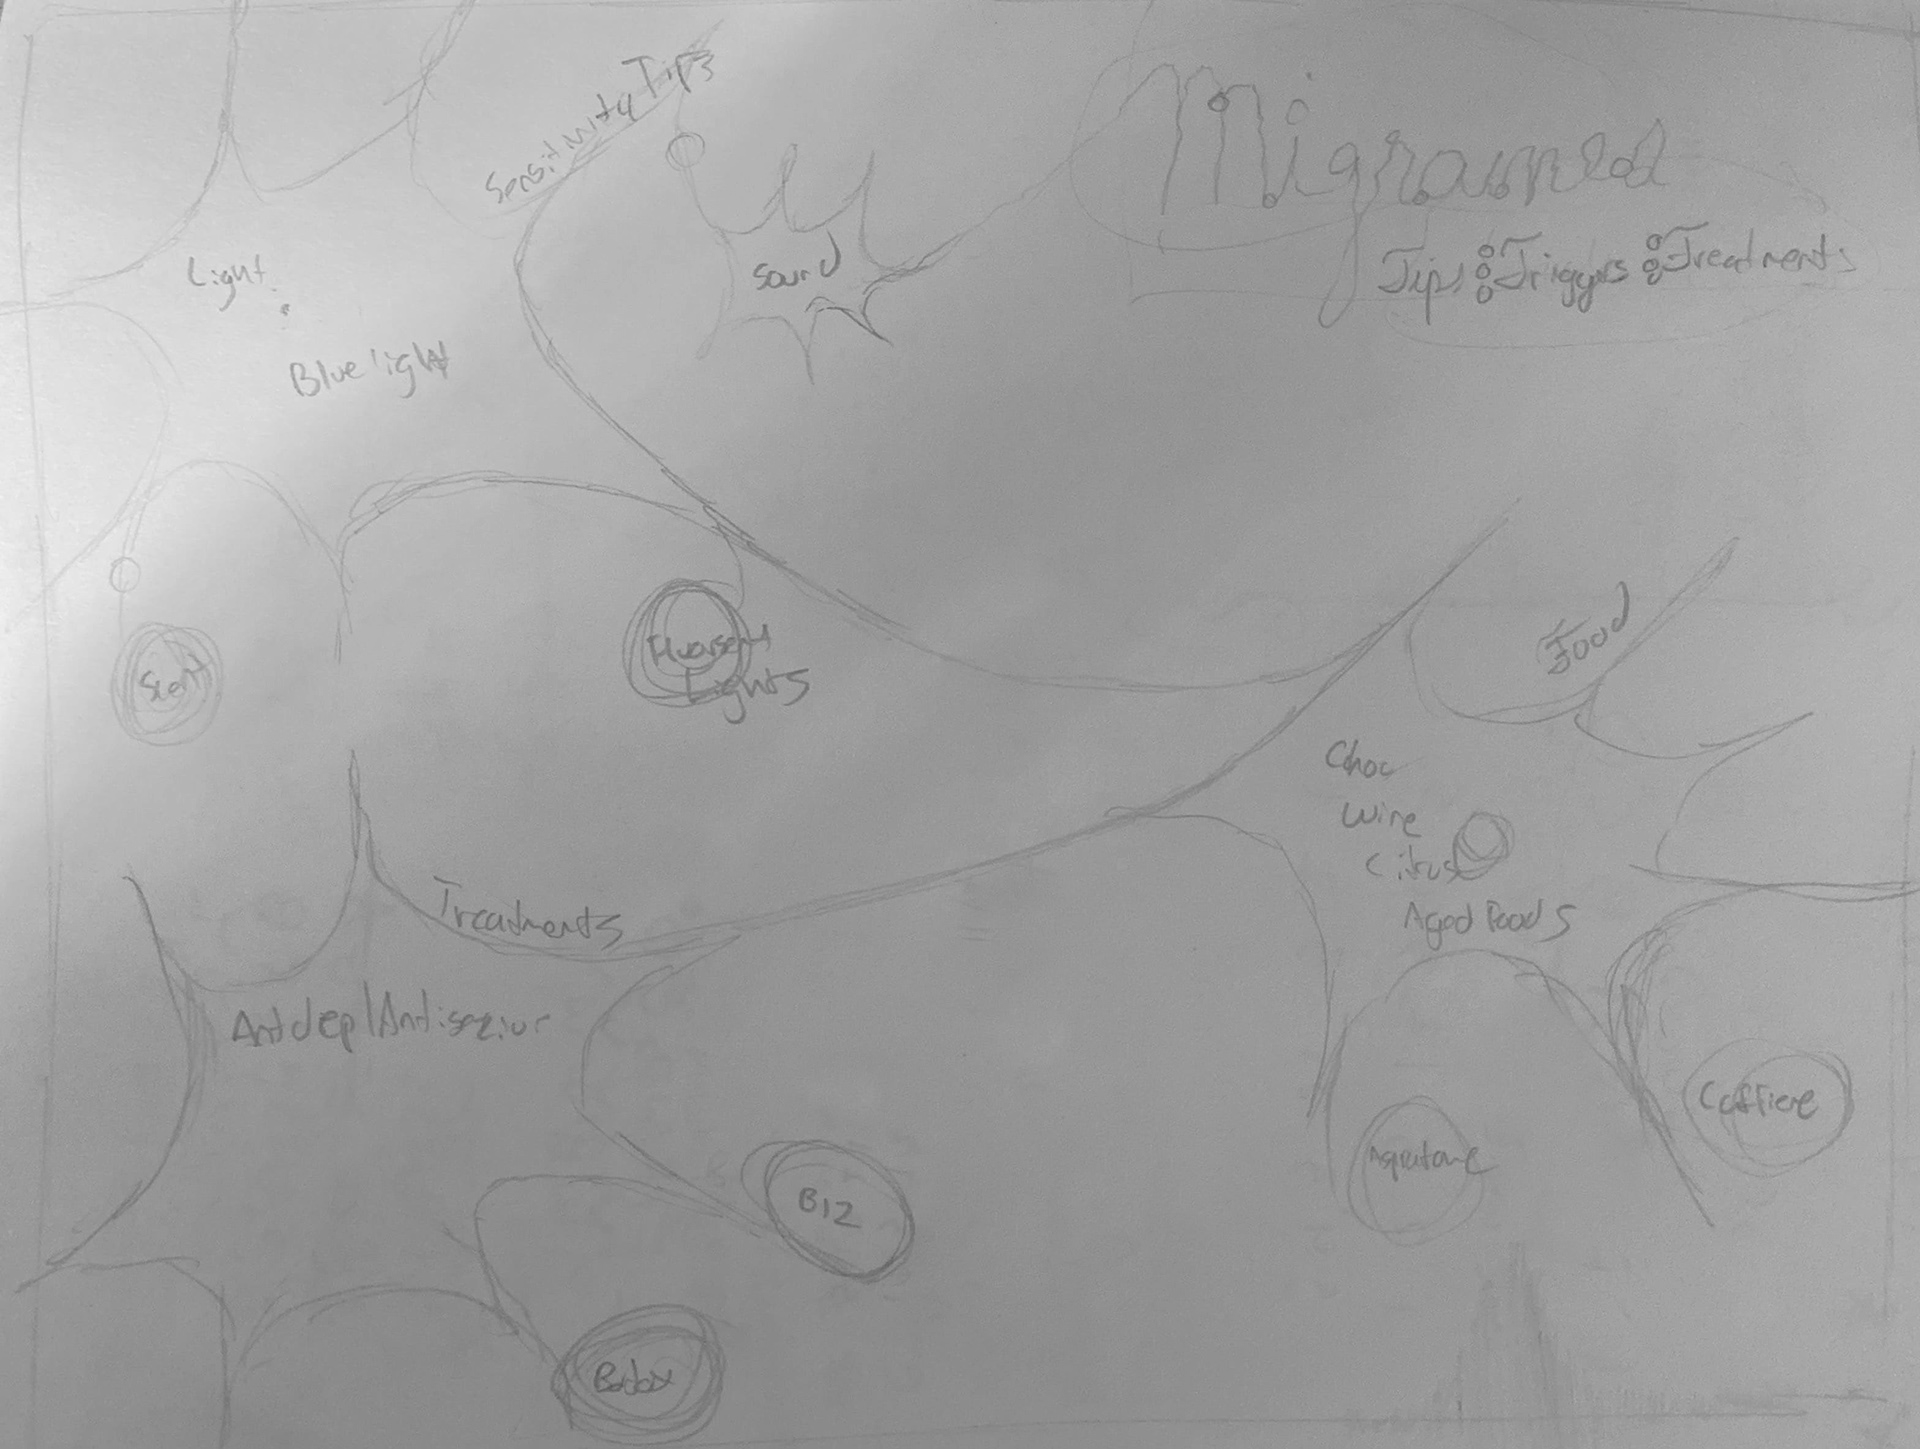

Migraines: Triggers: Tips: Treatments

A Very Different Take on Visually Depicting Migraines

This poster dedicated to migraines came almost a year before the Migraine Pack . Although each product has a unique visual language, there are a lot of commonalities within the two projects. Both projects aim to help solve and simplify care for migraine sufferers. There are so many solutions, every website has their own opinion of the right solution. Both projects aim to condense the information in a digestible way.

Digital Sketch One